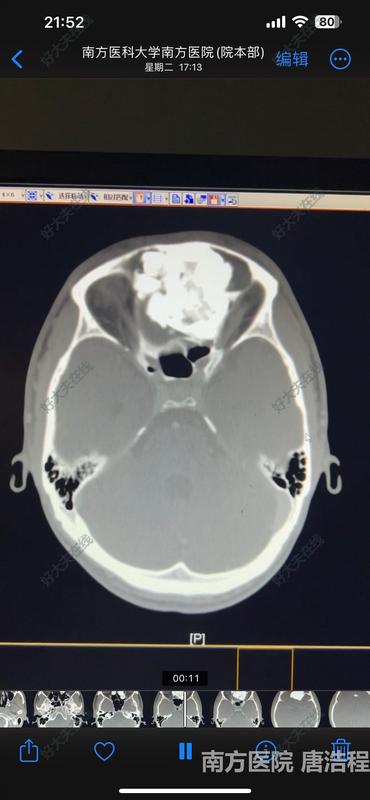

患者因“头痛伴有鼻部、眼部畸形”就诊,行鼻窦CT检查发现鼻窦前颅底眼眶巨大骨瘤,肿瘤占据双侧额窦、筛窦,突入颅内和左侧眼眶